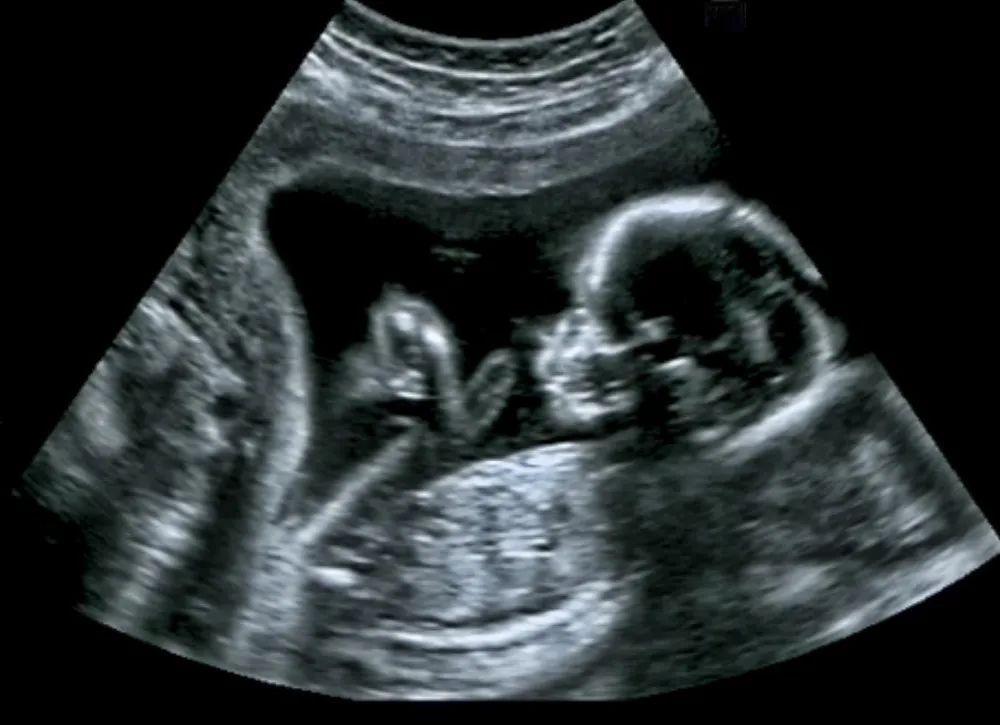

4. B 超:用超声波的反射快速检查

超声检查是用仪器发出超声波,然后用反射的回声来画像的检查方式。它是最为快捷、方便、低成本的检查手段,常常用于一些疾病的快速诊断,因为没有辐射成为孕检的标配。

但超声本身也有缺点,一些较深或有骨性结构遮挡的脏器难以检查,对图像的判断也很依赖医师经验。